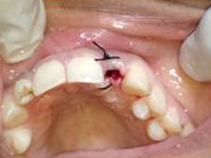

Drilling for Implant

Placement of Bone Grafting

Implant with bone Graft

Suturing done